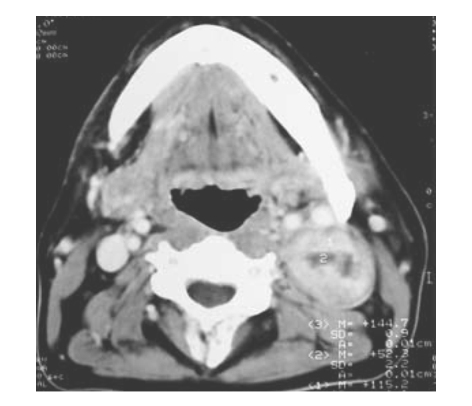

患者,女,43歲,發現左側頜下包塊2年多,近3個月明顯增大。行CT增強掃描如圖所示: